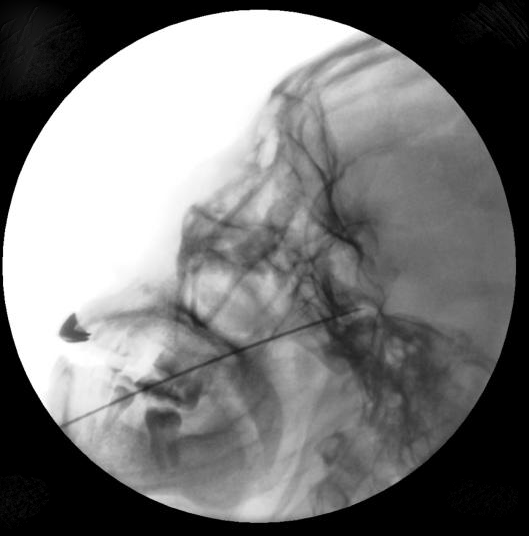

近日,首都医科大学附属北京朝阳医院(以下简称朝阳医院)疼痛科成功为一名长期受“原发性三叉神经痛”困扰的患者实施局麻下三叉神经半月结射频热凝微创手术。手术精准治疗,效果显著,患者现已康复出院。

朝阳医院疼痛科团队采用局麻下三叉神经射频热凝术,选择性调控三叉神经第二支和第三支,保留第一支功能。该技术具有治疗精准、患者配合程度高、即刻止痛、效果确切、组织损伤小、术后恢复快等优点,且无需承担开颅手术的风险。

射频热凝术是治疗三叉神经痛的重要方法,它包括三叉神经根脉冲刺激和温控凝固技术。热凝治疗前应用间断脉冲电流刺激,进行感觉测试和运动测试,一方面了解刺激区与患者疼痛发作区是否吻合,另一方面尽可能降低对咀嚼运动功能的影响,使热凝变得更加精细和安全。由于传导痛觉的无髓鞘细纤维在70-75°C时就发生变性,而传导触觉的有髓鞘粗纤维能耐受更高的温度,温控热凝是将毁损温度控制在75°C,这样就能利用不同神经纤维对温度耐受的差异性,有选择性地破坏半月神经节内传导面部痛觉的细纤维,而保存对热力抵抗力较大的传导触觉的粗纤维,达到即刻止痛,又能保留咀嚼肌肌力和面部本体感觉的目的。

与传统全麻下热凝治疗不同,朝阳医院疼痛科采用局麻下热凝治疗,确保医患交流畅通,患者能准确描述射频仪发出刺激后的感受。经过四个周期的射频热凝治疗,患者未出现任何副作用,对治疗效果非常满意。